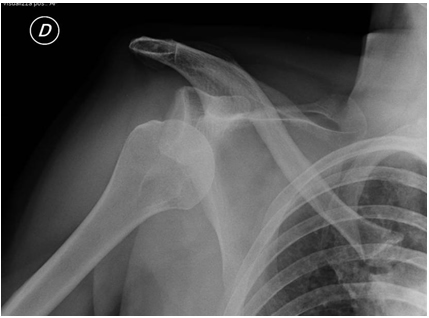

Nella scelta della tecnica di intervento influiscono diversi elementi: età, numero di lussazioni o, in assenza di queste, durata del dolore alla spalla e grado di impedimento durante l’attività sportiva o lavorativa, struttura muscolare, livello di carico durante il lavoro, pratica di sport o attività motorie a livello agonistico o amatoriale. Fondamentale è anche poter escludere la presenza di fratture associate alla lussazione e per questo un esame più approfondito con TAC o RMN può essere di grande utilità.